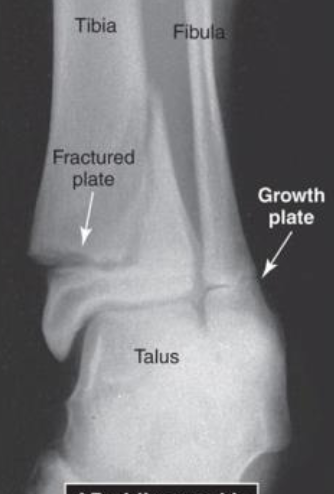

Example of Difficulties assessing Fractures in Children due to:

Growth plates

Dense growth lines

Secondary centers of ossification

Large nutrient foramina

Cartilage model not evident on radiograph

Salter-Harris Classification System for Epiphyseal Fractures

Type II MOST COMMON

15-20% of all fractures in children involve the growth plate

AP Oblique Ankle View of a Type II Salter Harris Epiphyseal Fracture at Distal Tibia